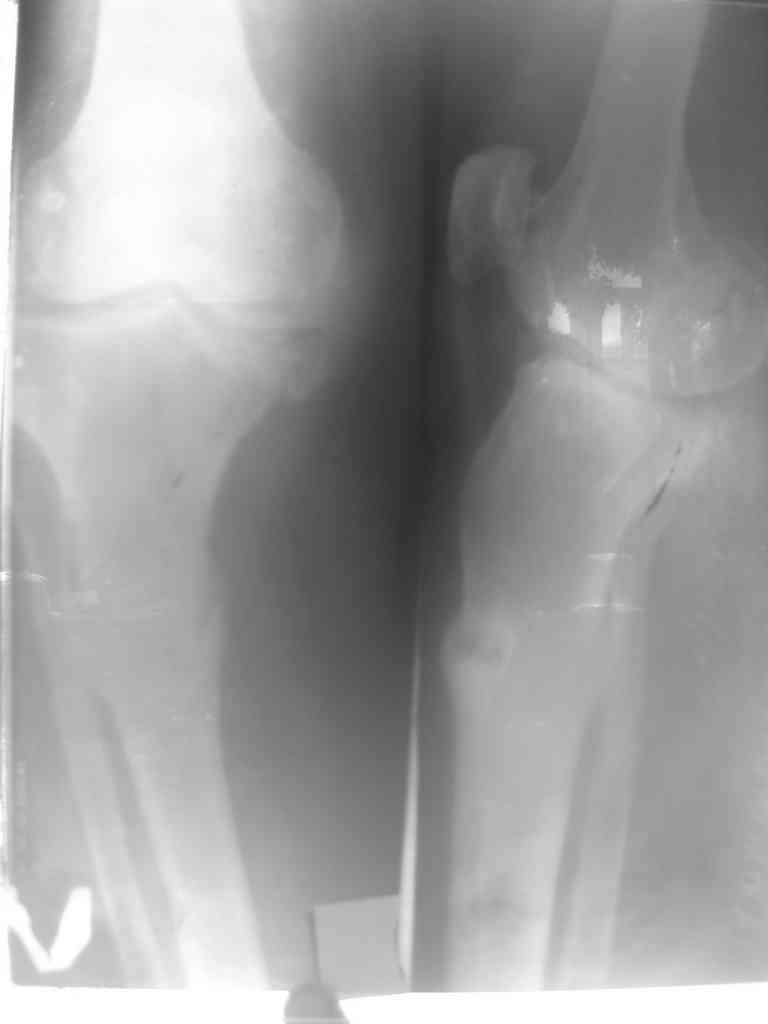

гипертрофический тугой ложный сустав

Глубокоуважаемые коллеги! Женшина 67лет.6месяцев назад упала.

после этого с болями но ходила с палочкой. постепенно появилась варусная деформация. боли усиливались. ходить стало трудно. Возможно это последствие остеопоротического перелома - ложный сустав? тактика лечения? Рентген снимок не очень качественная .